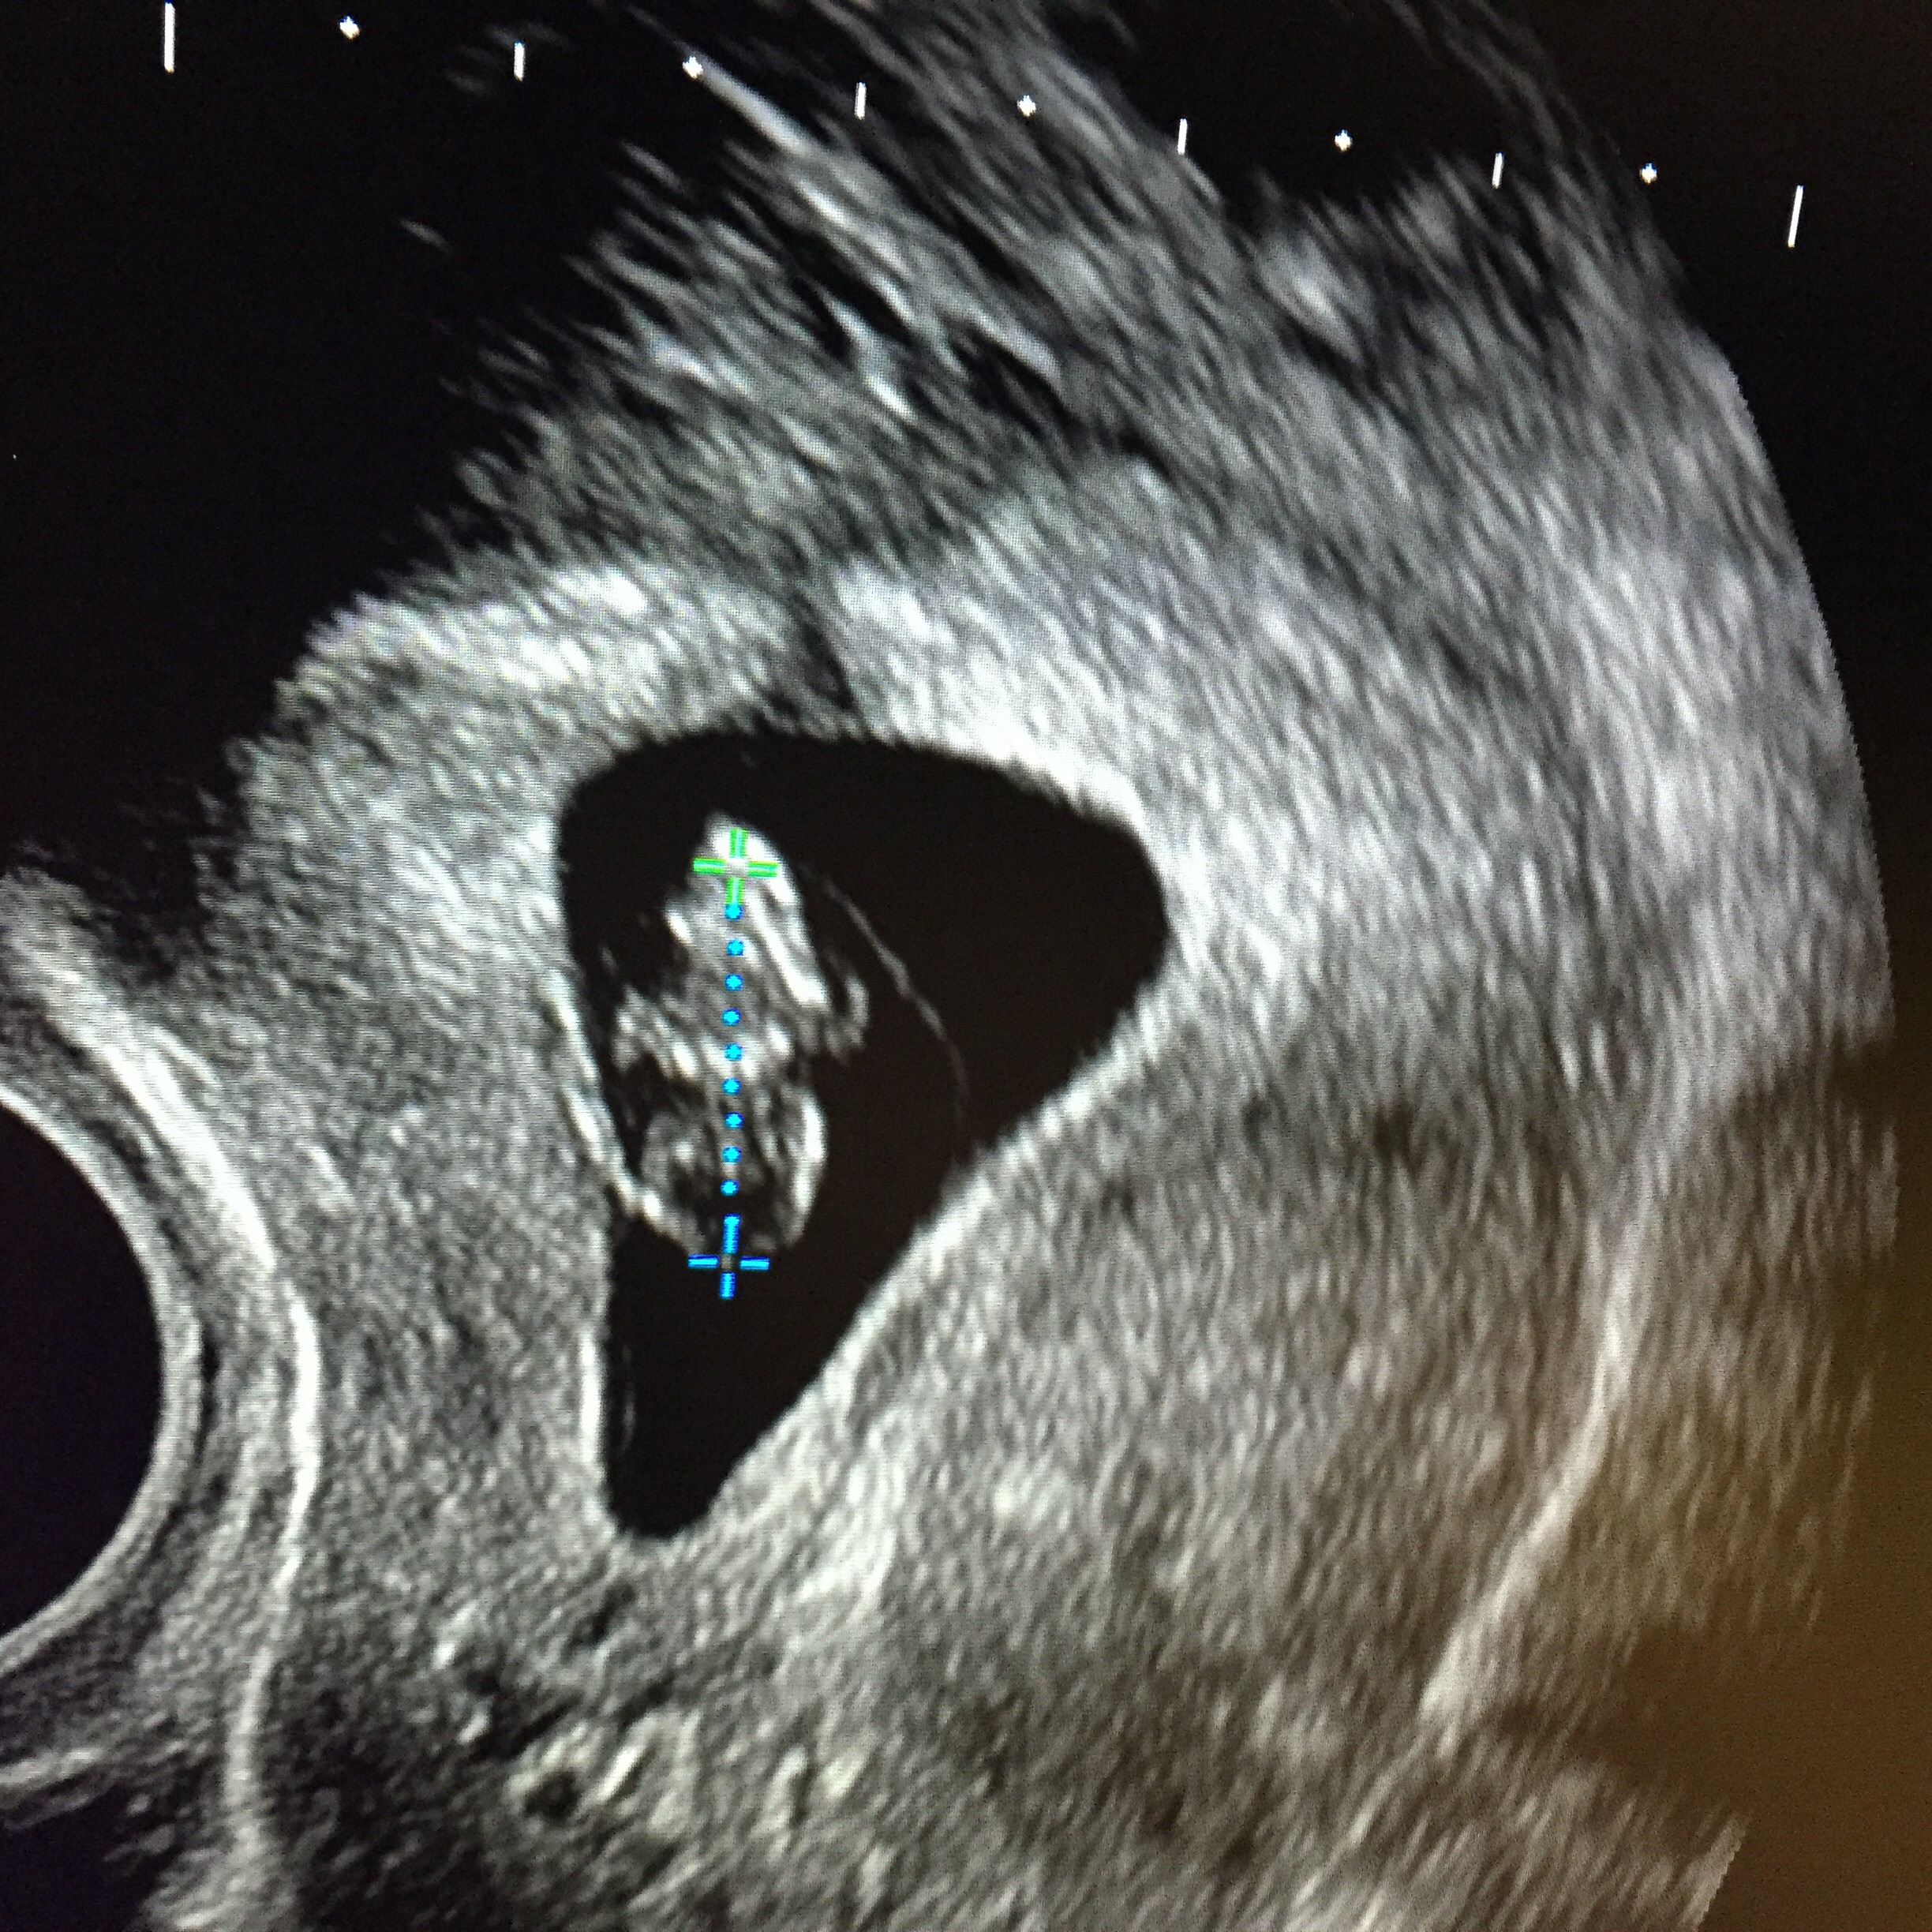

They had problems with my bladder being too full to the point I had to empty it like 3-4 times. Small bladder problems lol, but this is 7 weeks 3 days, now I'm 9 weeks and 6 days